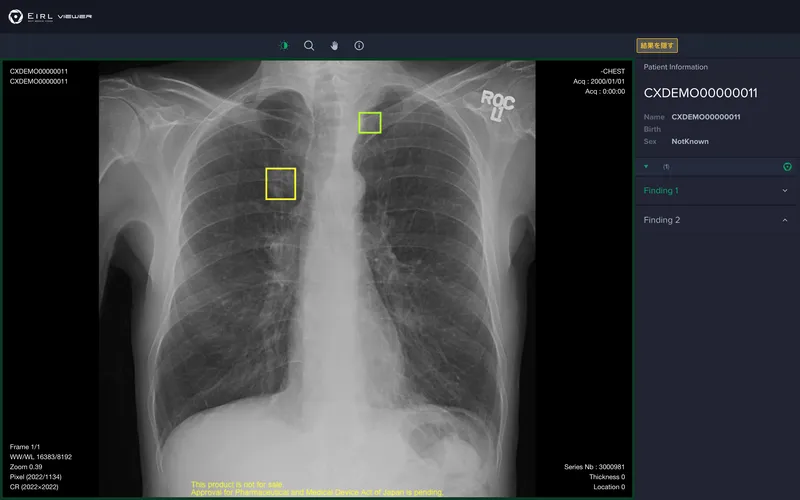

EIRL Chest Nodule

胸部X線画像から肺結節候補域を検出

X線透視診断装置又はX線診断装置の胸部単純撮影画像用のコンピュータ検出支援(Computer Aided Detection:CAD)機能を有し、医師の見落とし防止の支援を行います。さらに過去に撮影された同一被験者の画像と比較し、肺結節候補域の経時的変化(増減)を表示します。

・胸部X線画像から条件を満たす肺結節の形状に類似した領域(5mm〜30mmまで)[1]を検出し、医師による読影をサポートします。 ・過去に撮影された同一被験者の画像と比較し、肺結節候補域 の経時的変化(増減)を表示します。 [1]浸潤性でないもの、胸部内で他臓器との重なりがない候補域に限る。